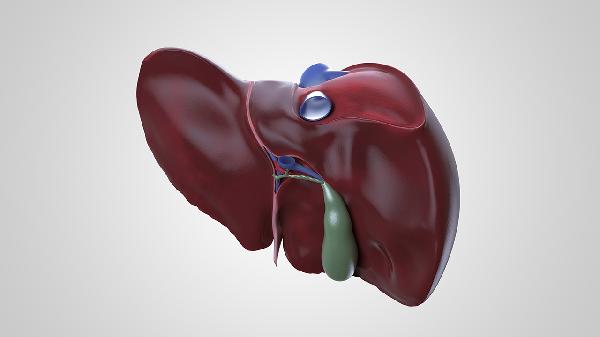

肝脏出现问题时,身体可能出现皮肤黄染、食欲减退、乏力、腹胀、尿液颜色加深等五种表现。这些症状可能与病毒性肝炎、脂肪肝、肝硬化、药物性肝损伤、胆道梗阻等疾病有关,建议及时就医检查肝功能、腹部超声等明确诊断。